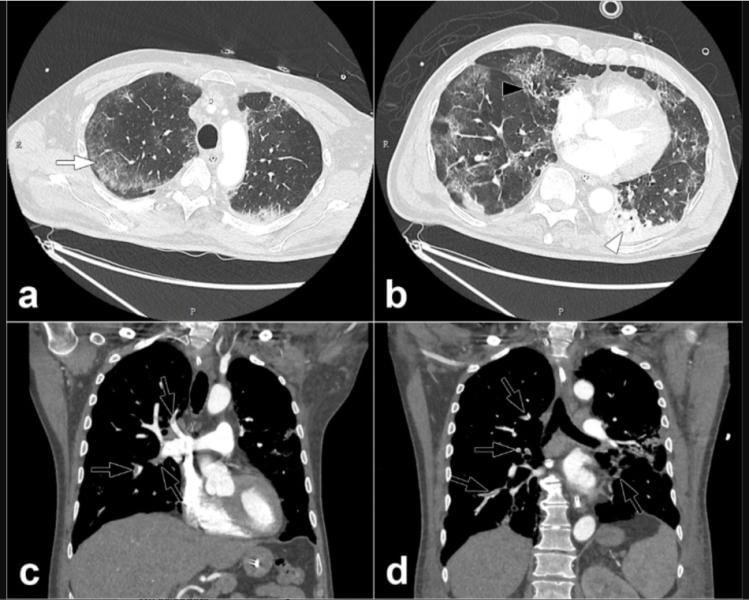

This photo gallery shows the variety of radiological presentations of COVID-19 (SARS-CoV-2) in medical imaging, including computed tomography (CT), radiograph X-rays, ultrasound, echocardiograms and magnetic resonance imaging (MRI). The radiology images show examples of typical COVID pneumonia in the lungs and the numerous complications the virus causes in the body in multiple organs, including the brain, kidneys, heart, abdomen and vascular system.

Ultrasound, especially hand-held ultrasound imaging devices, have become a primary imaging modality for novel coronavirus because of the ease to bag the device and sterilize it after use. CT and mobile X-ray systems are also used as front-line imaging systems for COVID-positive or suspected COVID patients.